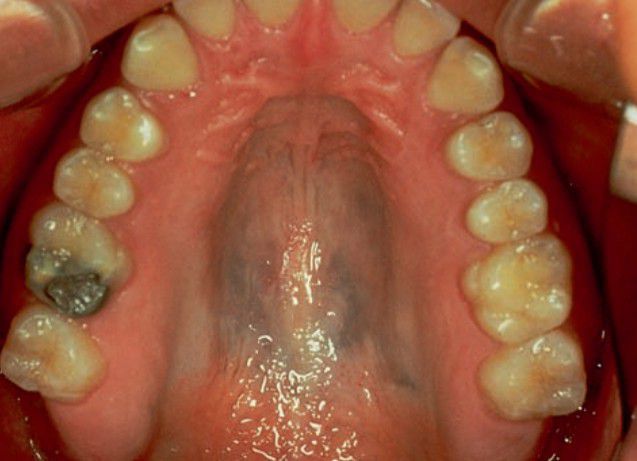

Drug induced pigmentation

This clinical picture represents minocycline induced pigmentation of palate.